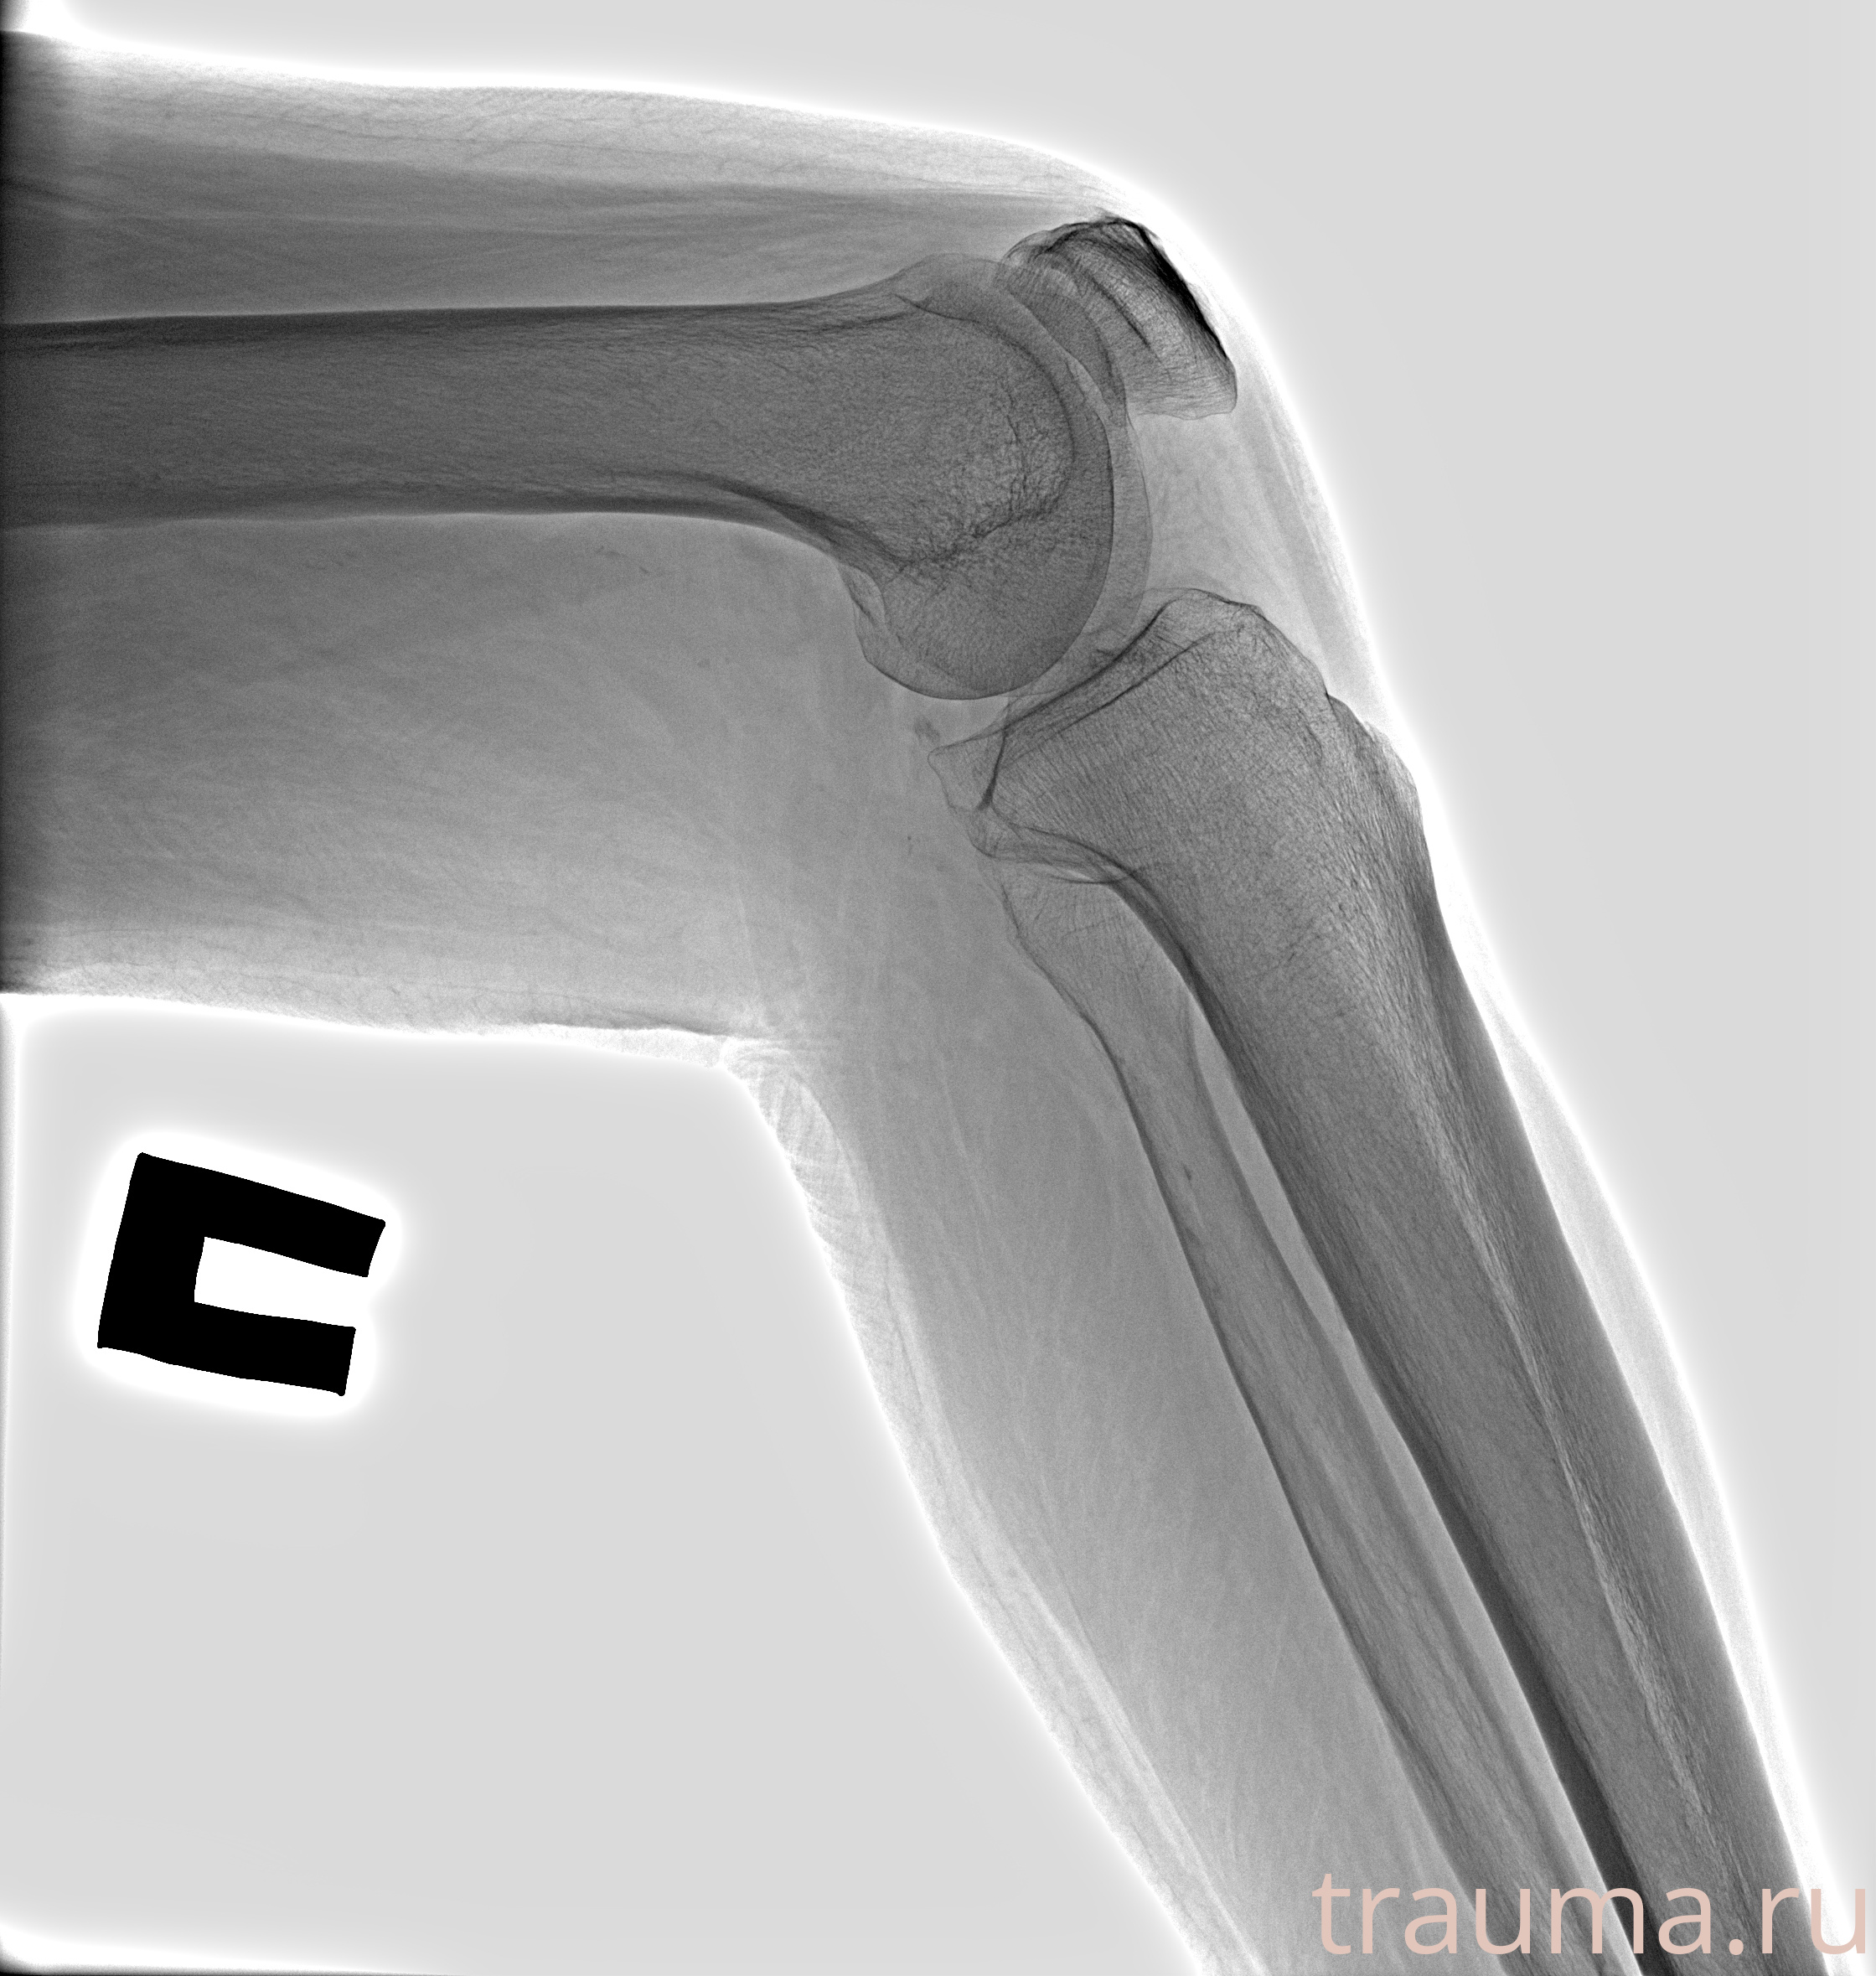

Рентгенограммы

Рентген на дому: по вашему адресу приезжает врач-рентгенолог, травматолог-ортопед с мобильным рентгеновским аппаратом, проводит диагностику травмы или заболевания, делает необходимые рентгенограммы, дает рекомендации по дальнейшему лечению. Получить качественные снимки в домашних условиях возможно благодаря уникальной методике, разработанной МосРентген Центром для института  Склифосовского